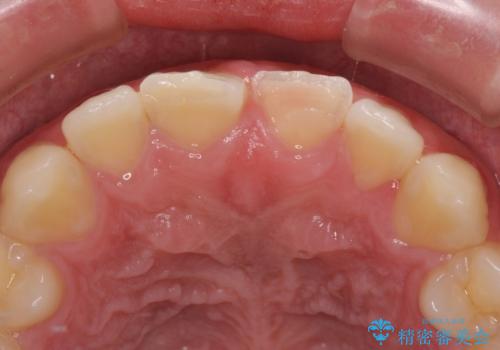

- 酔っ払って転んだらしく、目が覚めたら病室で歯が欠けていたとのことで来院された患者様です。

痛みを感じており、歯の欠けている状況から、神経組織のダメージも想定されました。

無菌的環境下にて歯の状態を調べ、最終的にオールセラミッククラウンにて補綴治療を行うこととしました。

幸いにも神経組織に影響はなく、健全な状態で治療を終えることができました。

歯肉の腫脹が目立っていたため、衛生指導も並行して行い、引き締まった歯肉になりました。